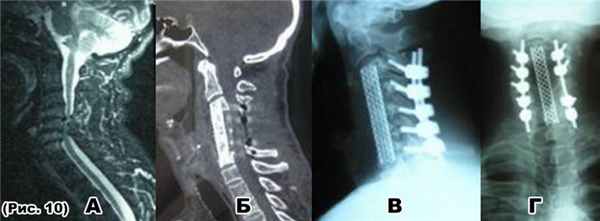

а) МРТ: дегенеративный стеноз позаоночного канала (90%) на уровне С4-С5-С6.

б),в) и г) КТ и R-граммыпосле декомпрессивно-стабилизирующей операции: ламинэктомия С4-С5-С6, задняя фиксации С3-С4-С5-С6-С7 позвонков и корпорэктомияС4-С5-С6 позвонков. Передний спондилодез мешем с аутотрансплантатом С3-С7 позвонков.